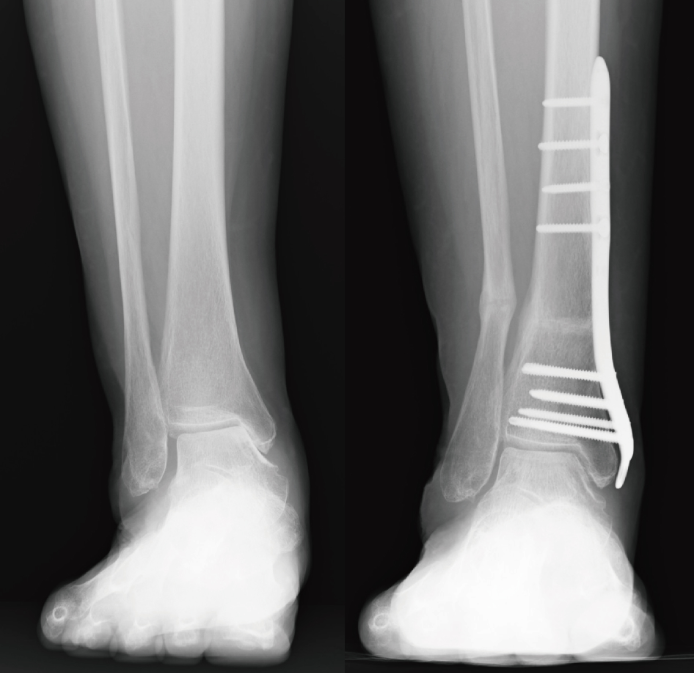

その中である程度変形しているものの程度が部分的な場合(多くの場合は内側)は「下位脛骨骨切り術」が実施されます。この骨切り術はすねの骨の足首に近い方を切って並びを矯正し足首の負担を軽くする方法です(図参照)。アライメントが改善されると痛みが軽減します。

↓下位脛骨骨切り術